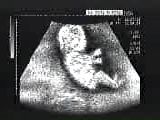

B超示胎兒2、頂臀長(CRL),又稱坐高,用於測量4周以及以後的胚胎;

目前用B超測量胚胎頂臀長度是較好的方法。